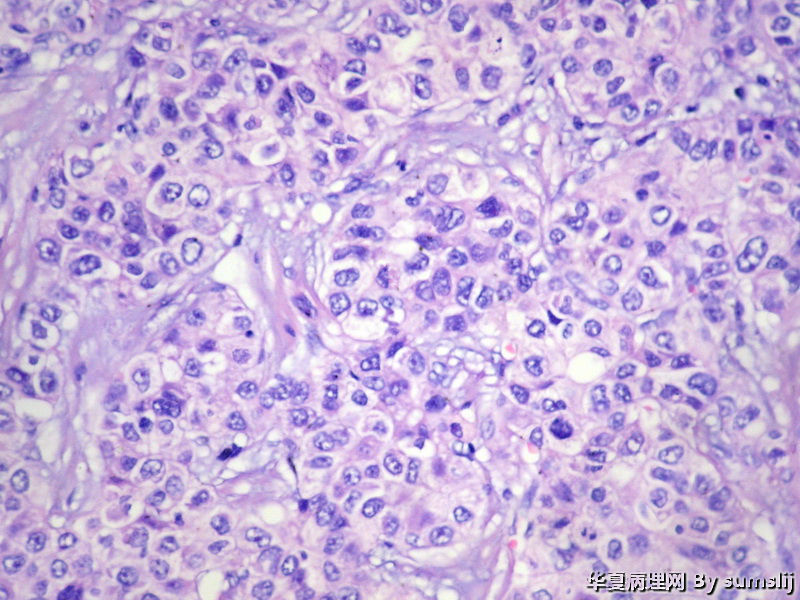

这是肝的混合性癌吗?

这是肝的混合性癌吗?图2

名称:图2

描述:IMG_2432

低分化肝细胞肝癌

肝细胞肝癌

肝细胞癌